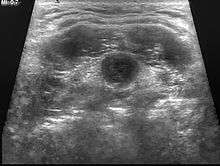

| Ultrasounds | Ultrasounds use high frequency sound waves to create images of blood vessels, tissues and organs through a computer to examine the degree of mass and its surrounding tissues. |